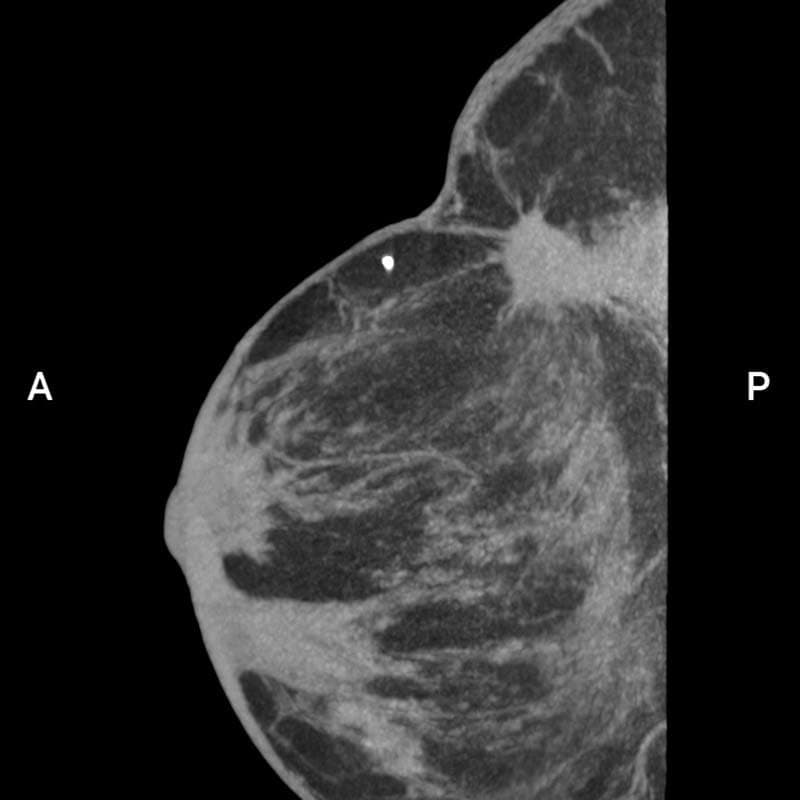

棘状病変(BI-RADS 3)

患者背景

• 60~69歳の女性

• 左乳房がん(浸潤性乳管がん、2001年、QUART)

• 左:組織構造の変形、棘状病変、手術後瘢痕

評価:BI-RADS 3

画像詳細

• 乳房側:左(L);再構成モード:高解像度

• 管電圧:60kV;管電流:32mA

• MIP:3.6mm

• ウィンドウ:C -50 / W 600

画像提供:アンドレアス・ボス教授(医学博士、医学博士)(USZ – チューリヒ大学病院)

棘状病変(BI-RADS 3)画像